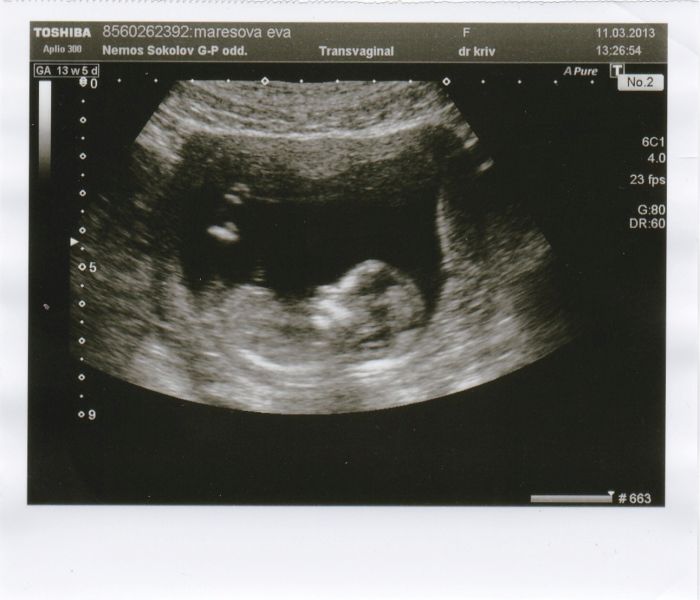

jinak taky vkládám fotečku toho našeho pupíčka ;-)

Evi - krásná fotečka

a pokud budete mít fotečky, tak se rády kouknem